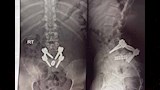

وأوضح جودة أنه عقب مناظرة الحالة من جانب فريق أطباء المخ والأعصاب بقيادة الأستاذ الدكتور هيثم المرسي، استشاري جراحات المخ والأعصاب والعمود الفقري، تقرر إجراء مجموعة من الفحوصات الطبية والأشعات اللازمة، والتي أوضحت إصابتها بتزحزح شديد بالفقرات القطنية والعجزية من الدرجة الخامسة، مصحوبًا باختناق بالقناة العصبية، وهي من الحالات النادرة والمعروفة طبيًا باسم L4-5 spondyloptosis.

أشار الدكتور هيثم المرسي إلى أنه تم تجهيز المريضة ونقلها إلى غرفة العمليات، حيث أُجريت لها جراحة دقيقة ومعقدة استغرقت نحو 7 ساعات. وشمل التدخل الجراحي إصلاح التشوه بشكل كامل، مع فك الضغط عن القناة العصبية وتحرير مخارج الأعصاب، تحت مراقبة جهاز المراقبة العصبية، مستخدمًا تقنية بولمان (Bohlman technique for spondylolisthesis).